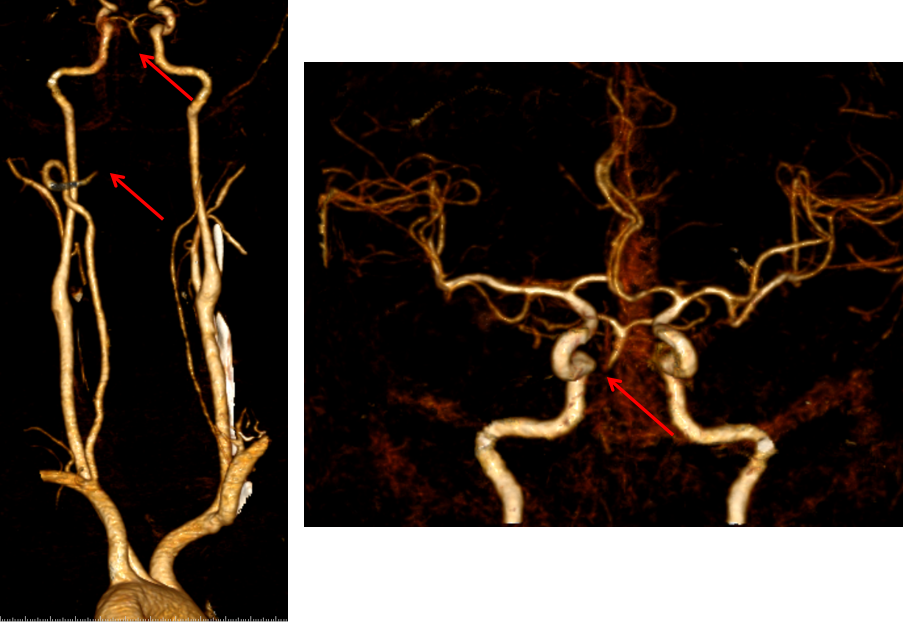

头颈部CTA:右侧椎动脉纤细,双侧椎动脉末端、基底动脉起始段消失,考虑闭塞,请结合临床。

入院头颅CTA(2022-2-2)

1、患者入院时症状较轻,头颈部CTA示:双侧椎动脉V4段及基底动脉中下段未显影,基底动脉上段、双侧大脑后动脉及小脑上动脉显影,考虑基底动脉存在原位狭窄或慢性闭塞,入院后患者病情进展,症状加重,积极行介入治疗。